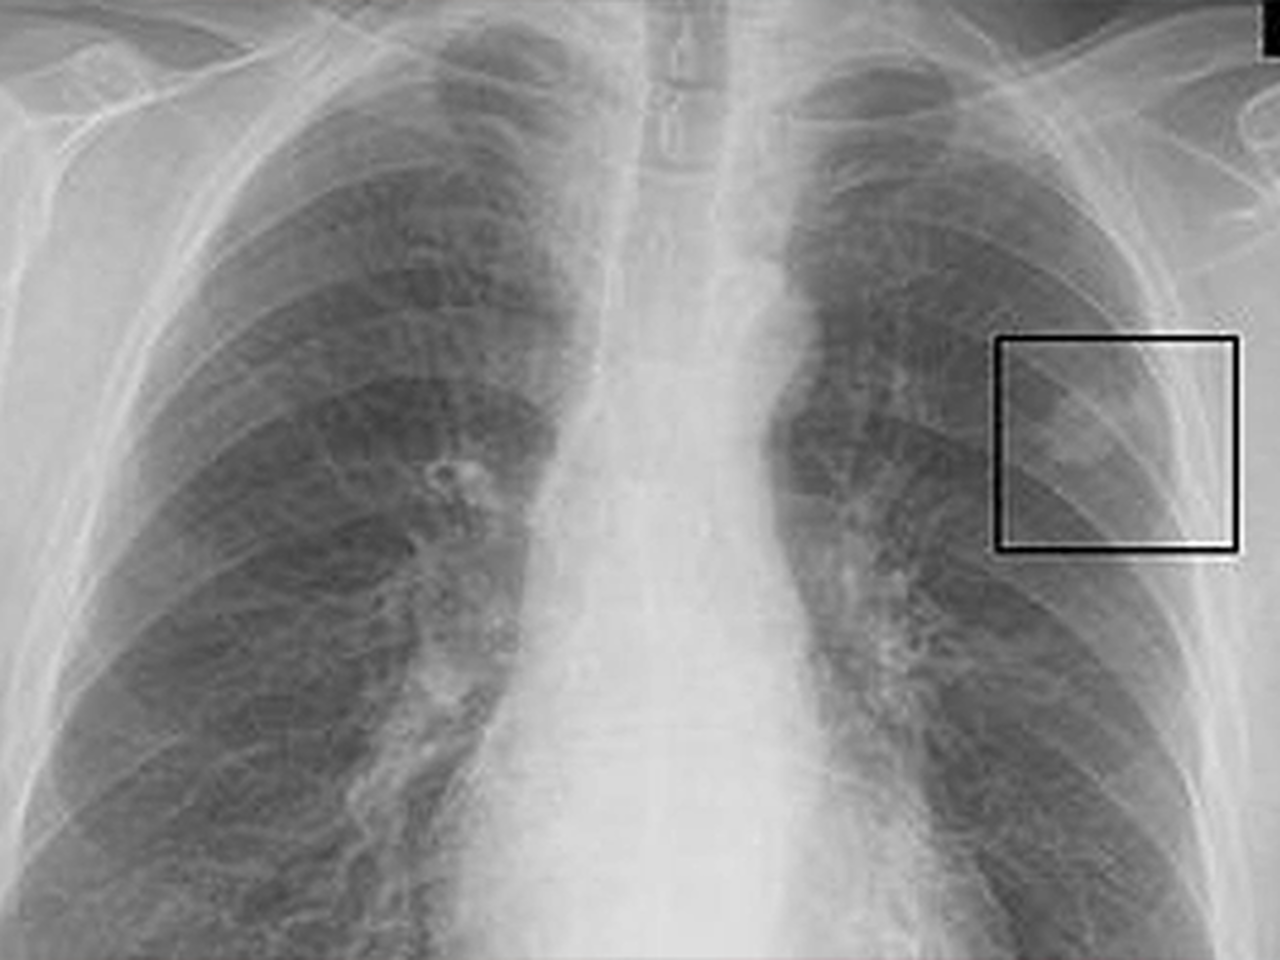

Doç. Dr. Özdemir, akciğer filminde görülen “leke” ifadesinin tıpta “nodül” olarak tanımlandığını belirterek, “Nodül, akciğer dokusundan farklı yapıda ve görüntüde olan alanları ifade eder. Akciğerde nodül oluşmasının birçok sebebi vardır. En sık karşılaşılan nedenler geçmişte geçirilen enfeksiyonlardır. Enfeksiyonlar akciğerde iz bırakabilir ve nodül şeklinde görüntü verebilir” dedi.

Tüm nodüllerin tehlikeli olmadığını vurgulayan Özdemir, asıl önemli olanın büyüme potansiyeli olan nodüller olduğunu söyledi.

“Bizim için risk taşıyan nodüller, zaman içerisinde boyut değiştiren ve büyüme eğilimi gösteren nodüllerdir. Bu nedenle her nodül mutlaka hekim kontrolünde değerlendirilmelidir” diye konuştu.

“Özellikle ağır sigara içicilerde — bu durum 20 paket/yıl olarak tanımlanır — ve ailesinde akciğer kanseri öyküsü bulunan kişilerde nodüllerin düzenli takip edilmesi gerekir. Uluslararası rehberler doğrultusunda bu takipler yapılmakta ve hangi nodülün nasıl izleneceğine hekimler karar vermektedir.”